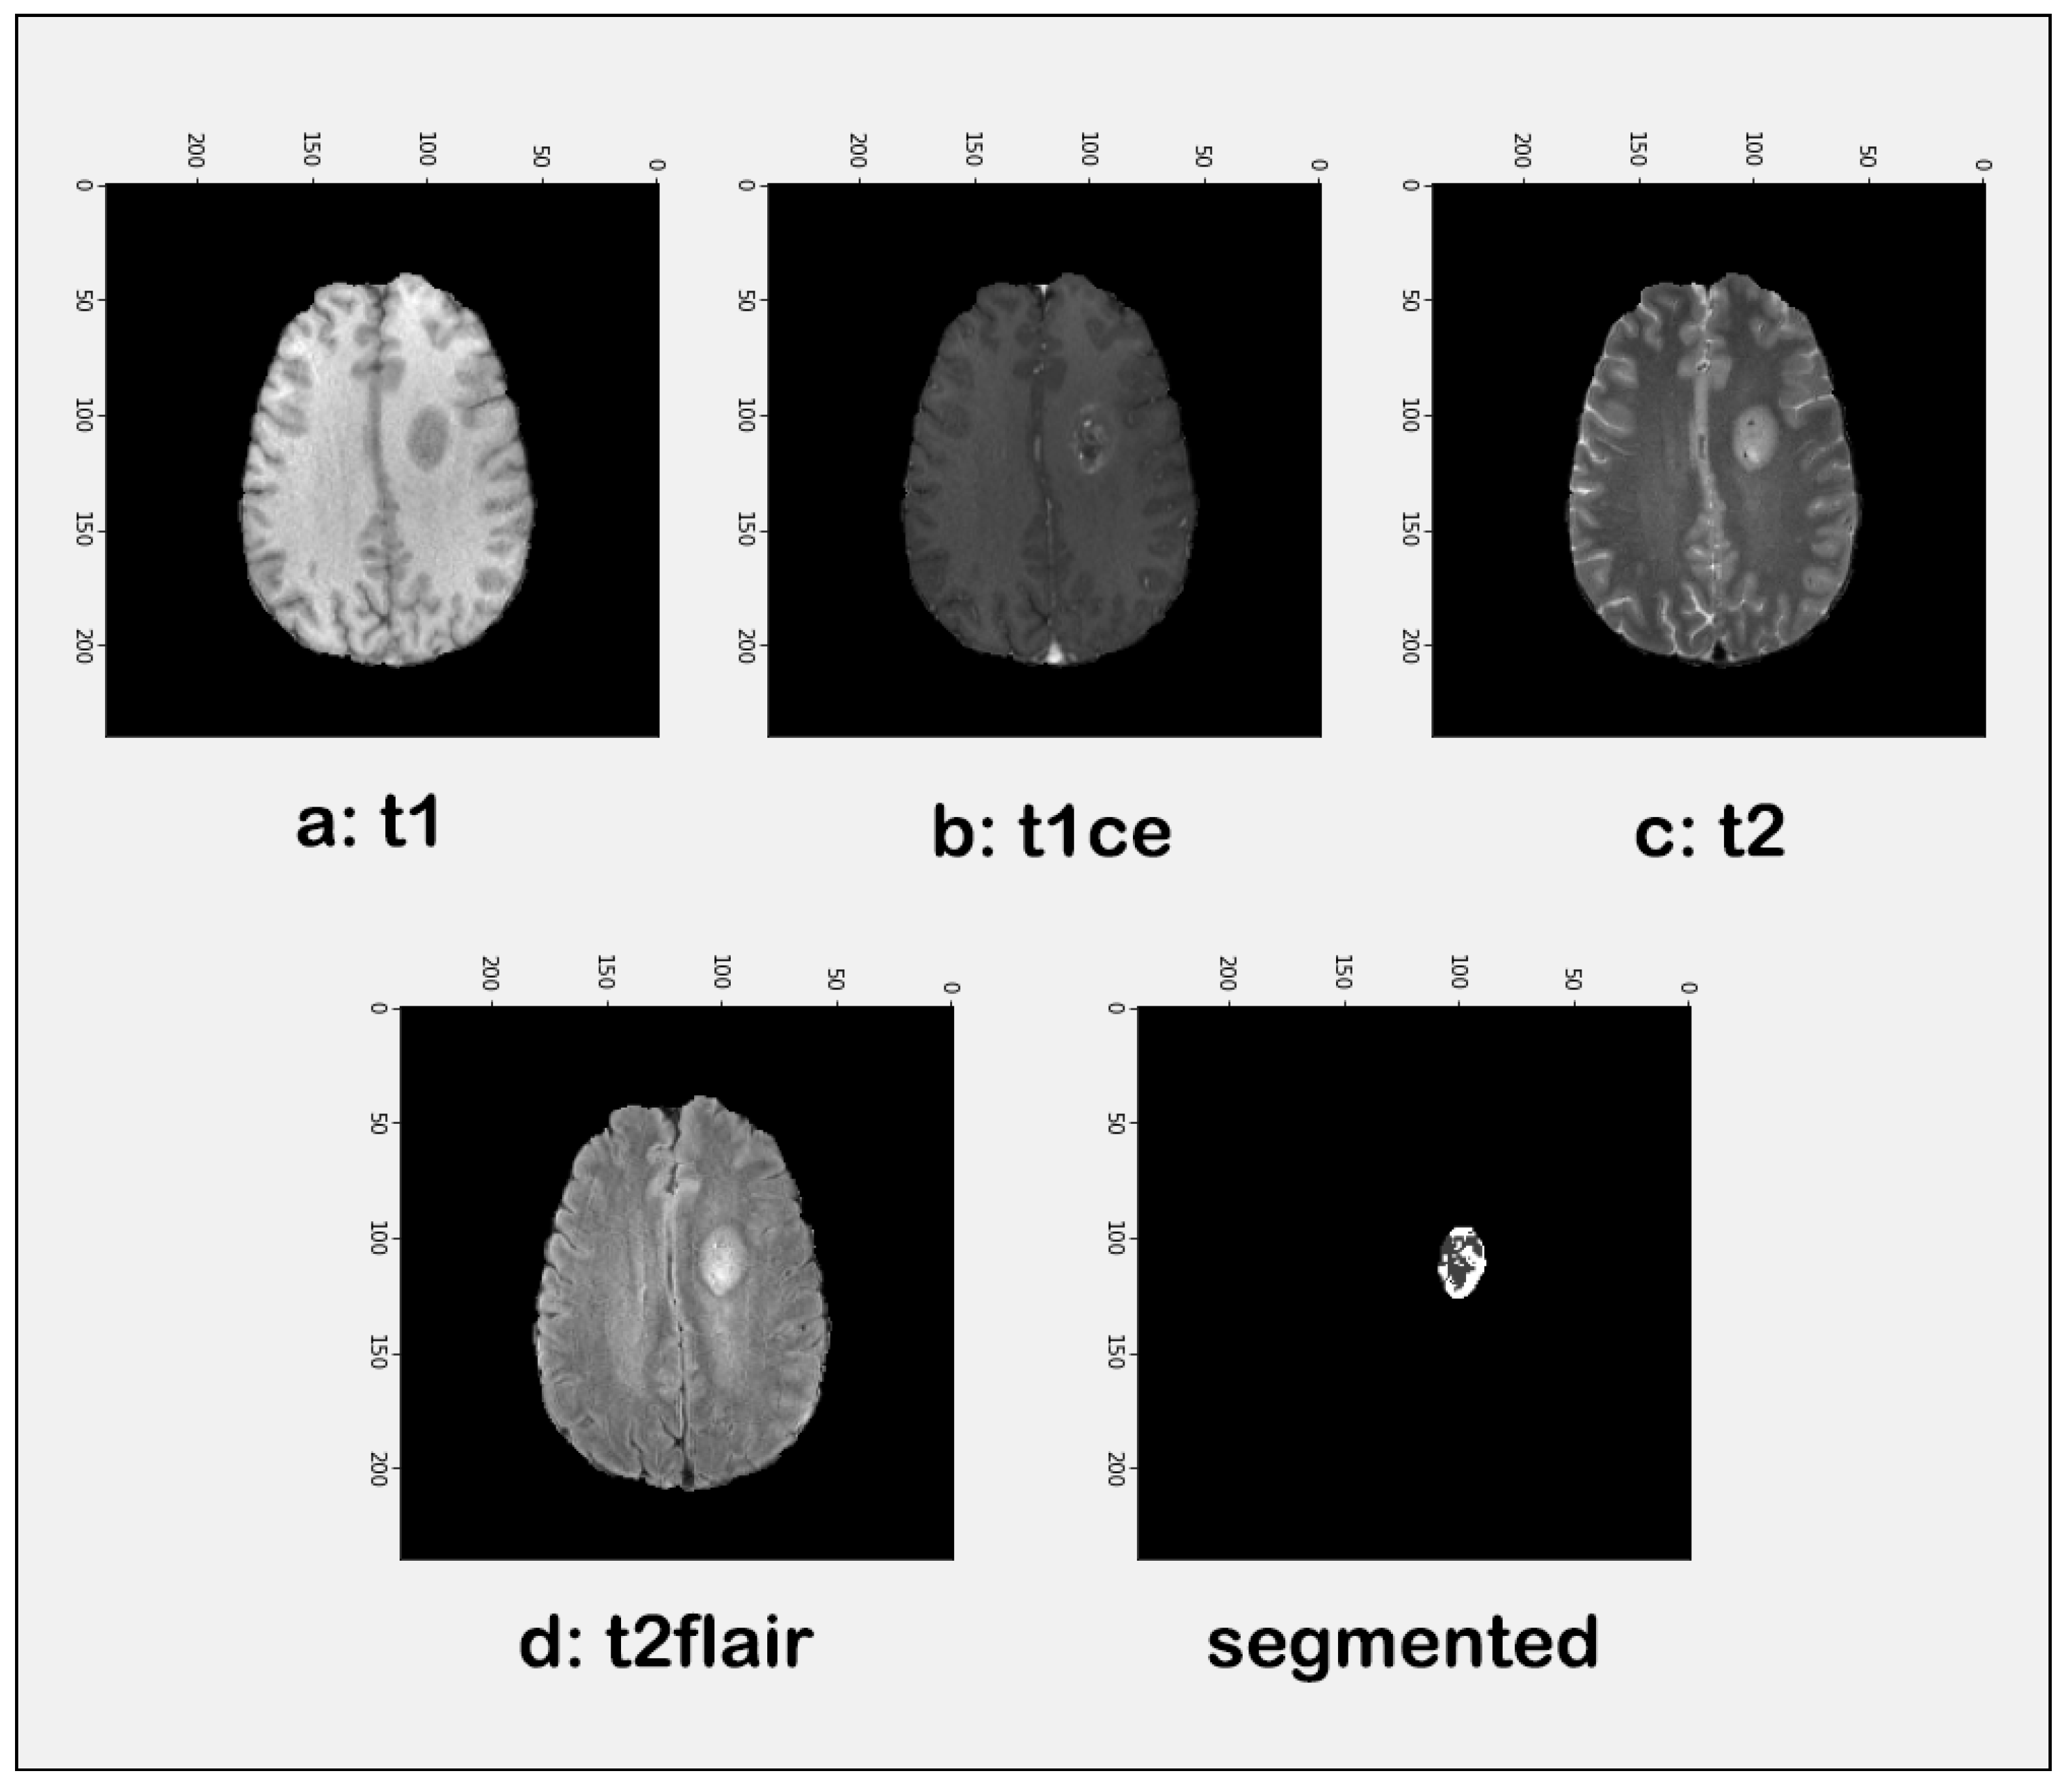

3.2. Tumor Identification

4.3.1. Tumor Identification